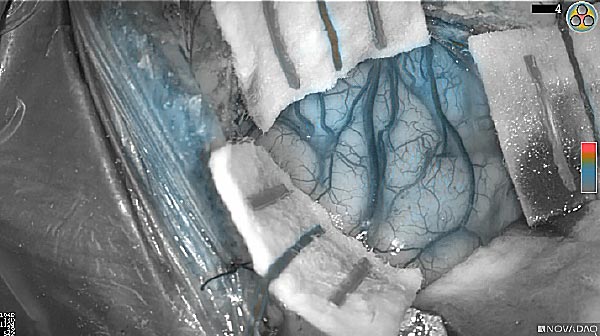

Near-infrared (NIR) labeled EGFR antibody, panitumumab-IRDye800, is systemically infused in high-grade glioma patients and specifically binds to tumor cells across the blood-brain barrier to improve intraoperative visualization during MRI-guided resection.

Skull Removed

Brain Exposed

Tumor Visible

Tumor Removed

White light

Fluorescence (heat map)

Fluorescence (black and white)

As the tumor was located beneath the brain surface (as indicated in presurgical MRI), minimal fluorescence was detected through the intact dura. The tumor lied beneath the area (dashed line: expected incision path) where faint fluorescence signal showed up on the brain surface. A clear fluorescence signal was visible in the tumor when the surgeon reached the tumor (dashed circle). Very little fluorescence remained in the wound bed after surgical removal of the tumor. You may also want to read the 2019 interview with Dr. Li and Dr. Rosenthal on novel imaging technologies to identify brain cancer.